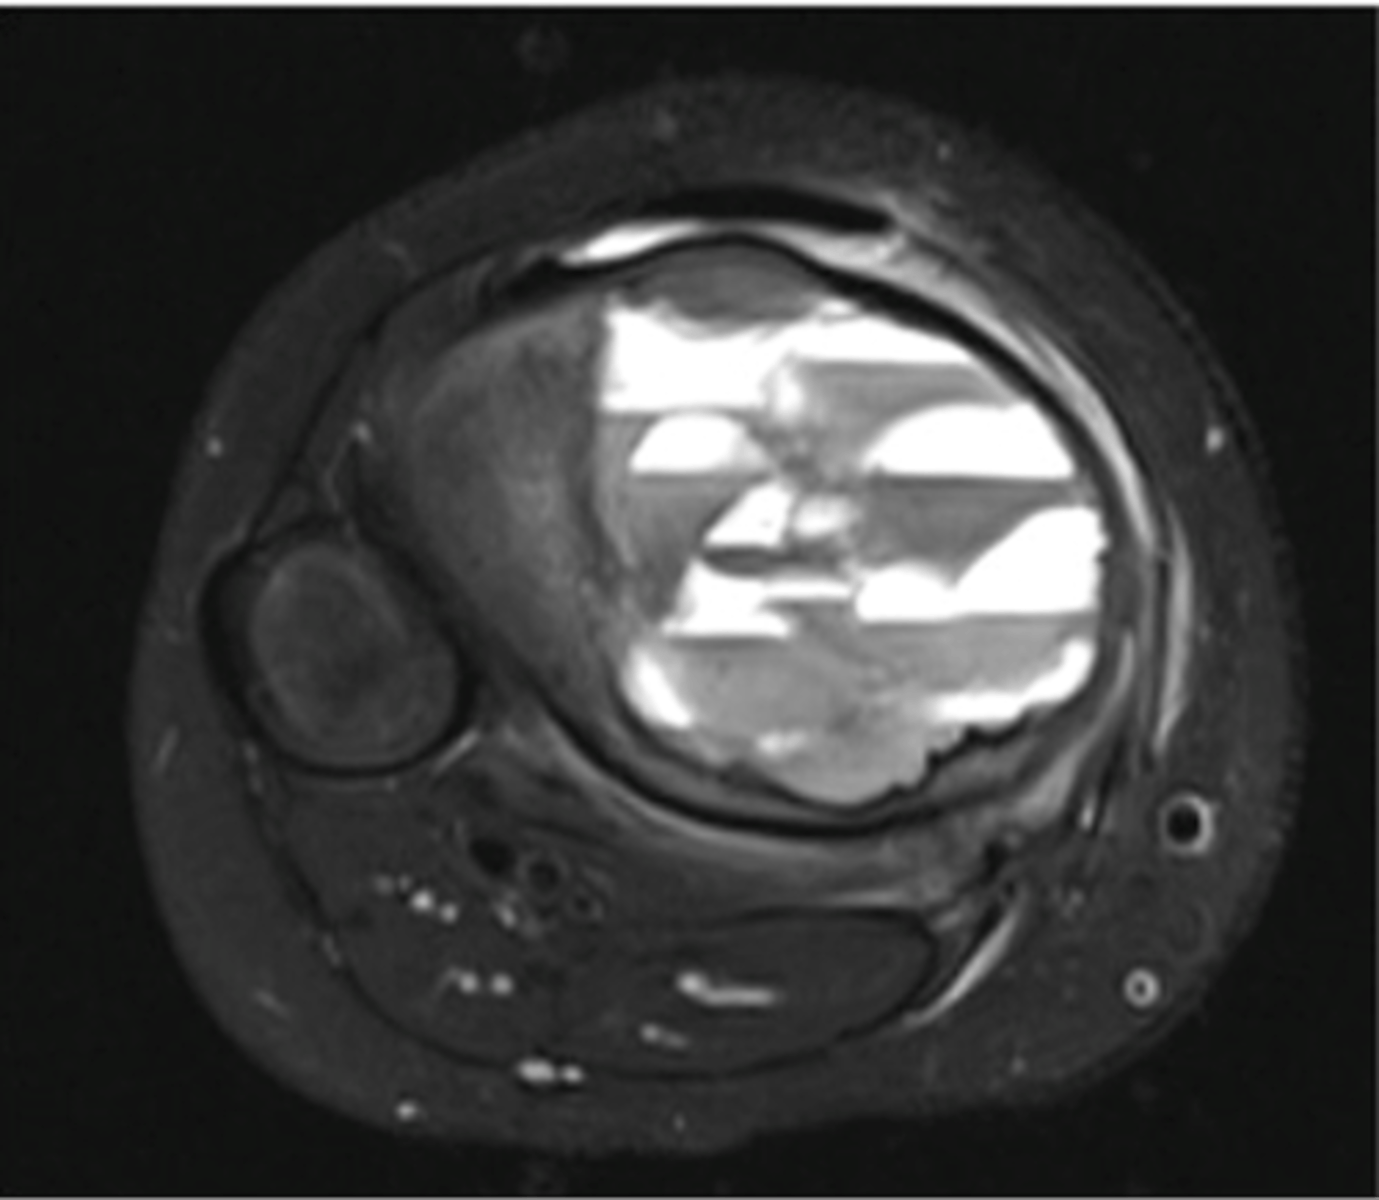

Aneurysmal bone cyst

- 1% of biopsied primary bone tumors

- M:F, 2:3

- 5-20 y.o.

- Acute pain

- Previous trauma

- 80% tubular bones and spine

<p>- 1% of biopsied primary bone tumors</p><p>- M:F, 2:3</p><p>- 5-20 y.o.</p><p>- Acute pain</p><p>- Previous trauma</p><p>- 80% tubular bones and spine</p>

67

New cards

- Eccentric

- Metaphyseal

- Osteolytic with fine trabeculae

- Saccular ballooning of cortex

- May cross epiphysis

- Periosteal buttressing

State the radiographic features of aneurysmal bone cyst in tubular bones

<p>State the radiographic features of aneurysmal bone cyst in tubular bones</p>

68

Fluid-Fluid Levels

- Most compatible with aneurysmal bone cyst

- Also seen in giant cell tumors, simple bone cysts, and telangiectatic osteosarcoma

<p>- Most compatible with aneurysmal bone cyst</p><p>- Also seen in giant cell tumors, simple bone cysts, and telangiectatic osteosarcoma</p>